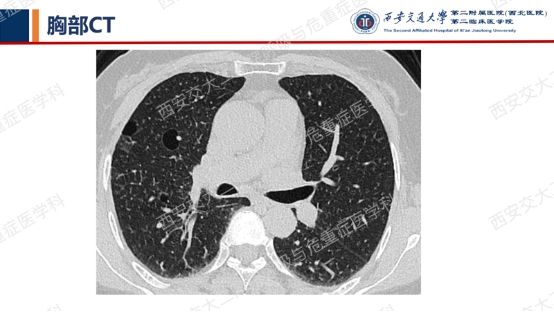

结合以上病史及胸部CT,您的初步考虑?还需要哪些检查?